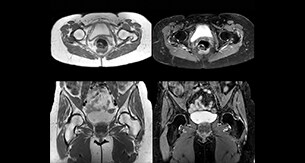

“In peripheral joints, we get good image quality in difficult areas with mDIXON TSE.

Fat suppressed images appear homogeneous over the entire image, even with large coverage at 3.0T – for instance in scapular or hip girdles – or in the bearing areas or around metal prostheses, where fat suppression is often deficient with STIR or spectral fat suppression, causing diagnostic difficulties. If a diagnostic image is right the first time, we don’t need to repeat or add a sequence.” “mDIXON TSE sequences allow simultaneous characterization of morphological changes from the in-phase T2-weighted images and visualization of edematous changes, thanks to the water T2-weighted images from the same acquisition. Anatomical and morphological considerations could be a partial or complete ligament tear, a bony avulsion or hematoma.” “For soft tissue assessment mDIXON brings similar benefits. For example in one T2-weighted mDIXON TSE acquisition, having the multiple contrasts helps us assess abnormalities in peripheral nerves fascicles, which may be due to anatomical or inflammatory changes..”